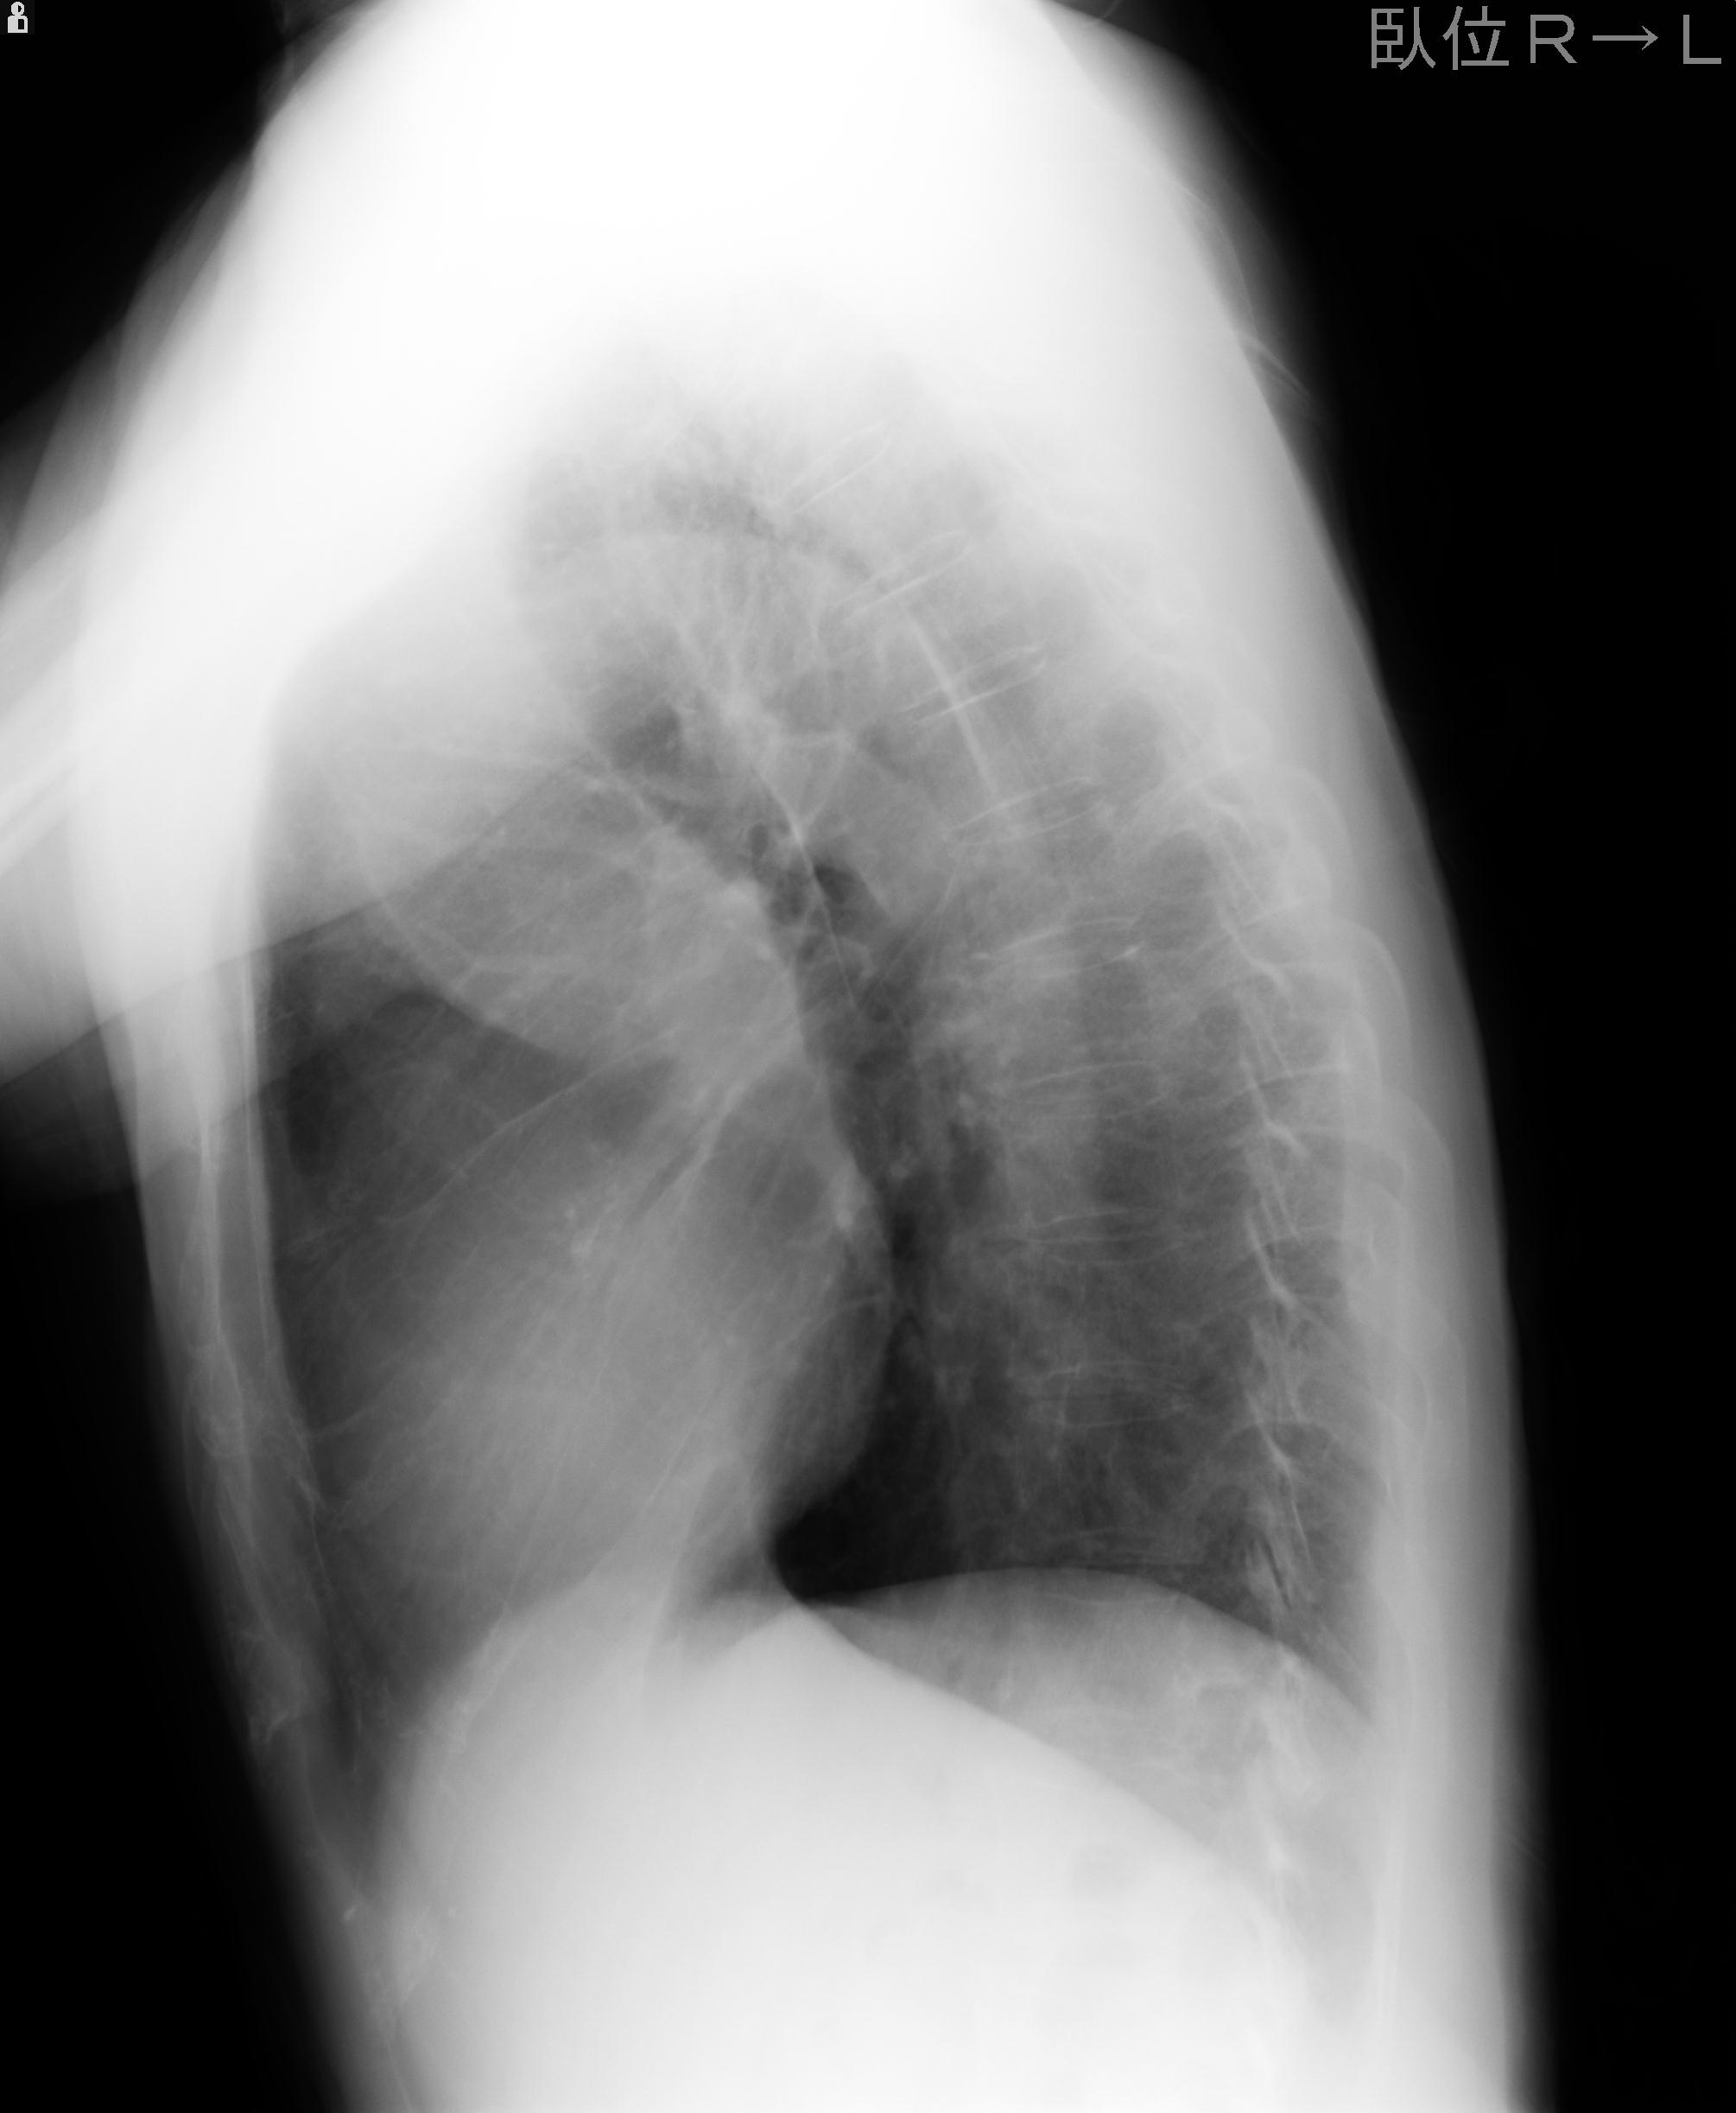

110214 12/20 肩 2R 12/21 肩 4R 72歳女性 左上腕外科頚プレート